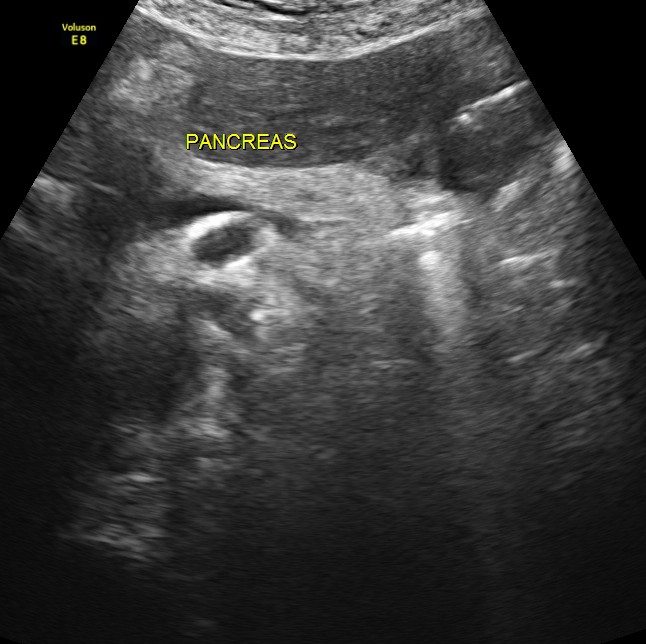

Pancreas appears normal.